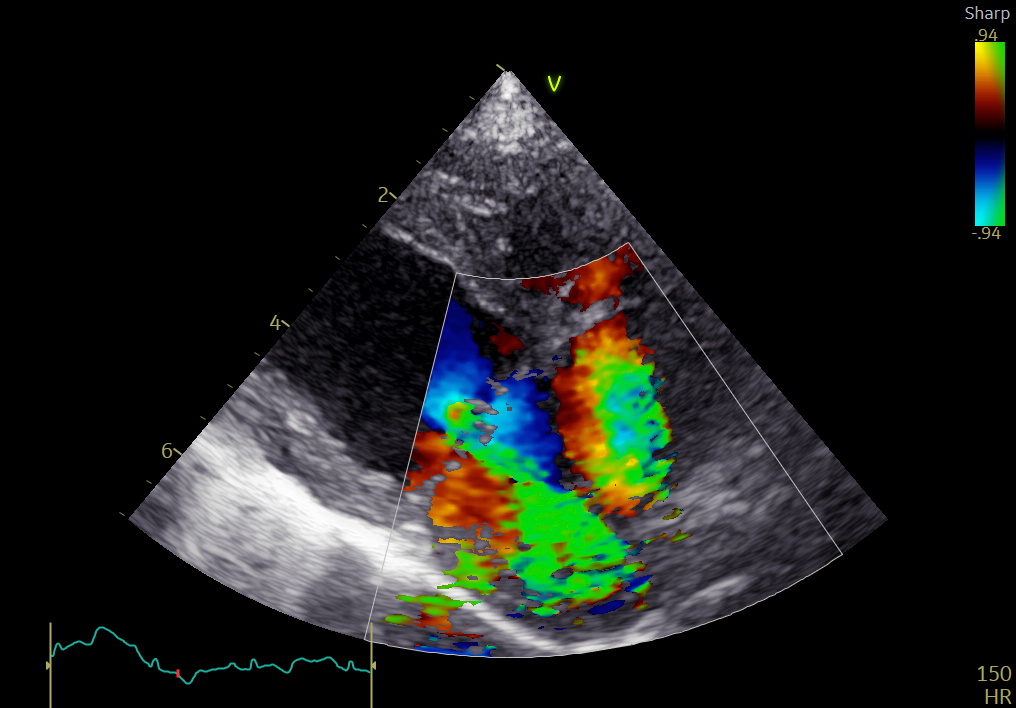

手術後

• 僧帽弁逆流は消失

• LA/Ao:1.43

• LVIDDN:1.62

術後3か月:

• LA/Ao:1.29

• LVIDDN:1.40

心拡大は明らかに改善し、内服薬はすべて中止となりました。

術後6か月現在も、臨床徴候なく安定しています。